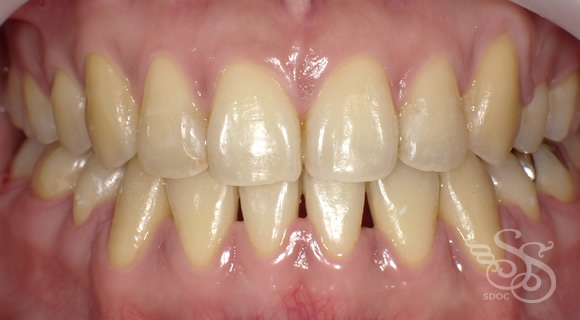

久しぶりに会った友人に「整形した?」と言われた患者さま

術前

術後